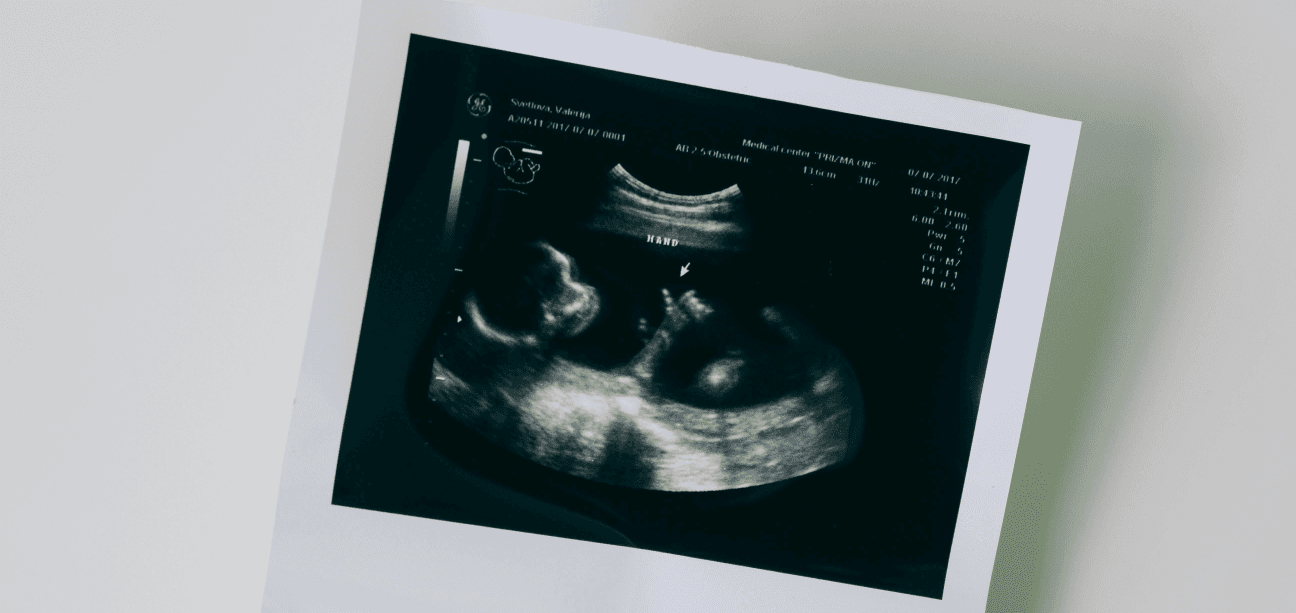

শিশু ব্রিচ পজিশনে আছে কি না সেই ব্যাপারে নিশ্চিত হতে ডাক্তার আপনাকে আল্ট্রাসাউন্ড করানোর পরামর্শ দিবেন